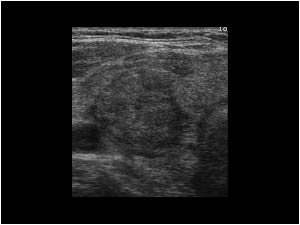

New cards

what thyroid pathology is shown here?

colloid cyst

93